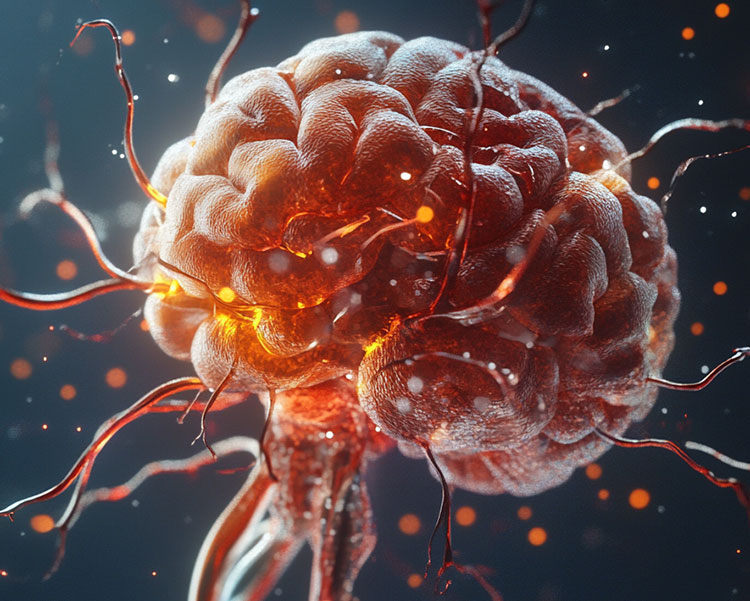

CollectiveX AI: Revolutionizing Medical Diagnosis and Treatment Planning

Discover how CollectiveX's AI-powered platform is enhancing diagnostic accuracy and treatment planning. By combining global medical expertise with advanced artificial intelligence, we're improving patient outcomes and revolutionizing healthcare delivery.